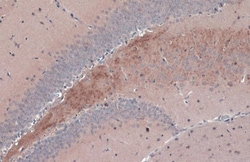

Keep as concentrated solution. Predicted reactivity: Mouse (100%), Rat (100%), Dog (100%), Cat (100%), Pig (100%), Chimpanzee (100%), Bovine (100%). Positive Control: mouse brain, rat brain, BDNF-transfected 293T. Store product as a concentrated solution. Centrifuge briefly prior to opening the vial.

| Immunohistochemistry (Frozen), Immunohistochemistry (Paraffin), Western Blot, Immunocytochemistry | |